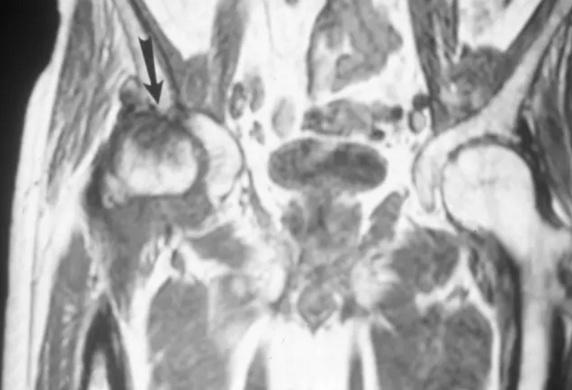

股骨头缺血坏死

冠状T1加权磁共振图像显示在股骨颈近端的低信号和表示造血骨髓的转子间区域(箭头)。